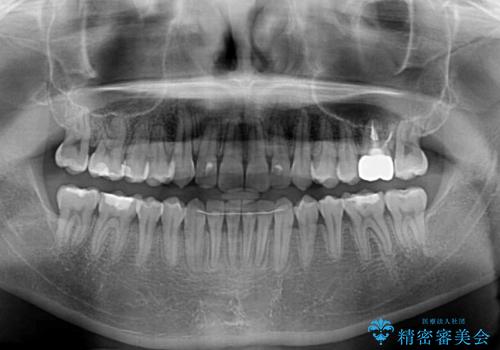

ディープバイトと叢生 インビザラインによる矯正治療

- 前歯のディープバイトと叢生を気にして来院された患者様です。

上下ともに叢生が認められたため、親知らずすべてを抜歯し、歯列全体を後方へ移動させることで歯列を整えることとしました。

上顎奥歯の銀歯も気になっていたので、矯正治療の途中でセラミッククラウンへ変更し、その後歯列を仕上げていくこととしました。